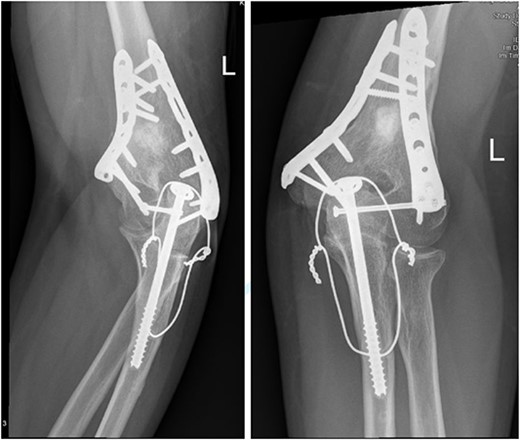

Anteroposterior (AP) view of the left humerus and elbow after ORIF.

The patient underwent left open reduction and internal fixation of proximal and distal humerus under general anesthesia. The patient was placed in the lateral position. Preparation and draping in the usual sterile manner were performed and a sterile tourniquet was used. The distal humerus was first approached through a posterior approach. Ulnar nerve protection and olecranon osteotomy was done, showing simple distal intraarticular fracture with minimal metaphyseal comminution. Anatomical reduction of the articular fracture was achieved, with preliminary fixation by k-wires holding the intra-articular fragments. This was followed by interfragmentary screw fixation from medial to lateral. Dual plate fixation (posterolateral and medial anatomical plates) was used to fix both medial and lateral columns, connecting the articular fragment to the metaphyseal. Reduction was confirmed under x-ray. Joint was tested for any screw penetration, and none was found. The osteotomized olecranon was reduced and fixed with cannulated screws and tension bands. The ulnar nerve was protected throughout the whole procedure and was reduced back into the cubital tunnel. Range of motion was examined; full range of motion was achieved. Finally, closure was done in layers.

The patient was then shifted from lateral to beach-chair position, and preparation and draping were repeated. A deltopectoral approach was utilized reaching to the proximal humerus. Reduction was achieved, followed by preliminary fixation with k-wires. Philos plates were used to fix the fracture. Range of motion was examined afterward, with no struggles detected. Fluoroscopic images were taken later to make sure no screws had penetrated the joint. Closure in layers was done, followed by dressing and application of an arm sling.